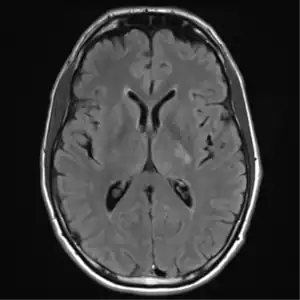

MRI brain: cryptococcus

Brain

Cryptococcal meningitis (infection of the meninges, the tissue covering the brain) is believed to result from dissemination of the fungus from either an observed or unappreciated pulmonary infection. Often there is also silent dissemination throughout the brain when meningitis is present. Cryptococcus gattii causes infections in immunocompetent people (fully functioning immune system), but C. neoformans v. grubii, and v. neoformans usually only cause clinically evident infections in persons with some form of defect in their immune systems (immunocompromised persons). People with defects in their cell-mediated immunity, for example, people with AIDS, are especially susceptible to disseminated cryptococcosis. Cryptococcosis is often fatal, even if treated.[19]